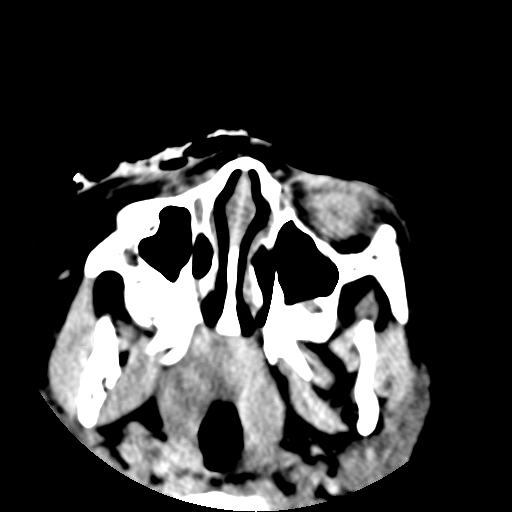

以下是引用深泽交通医院在2009-10-16 8:25:00的发言:[br]右眼环出血伴异物

以下是引用卜一在2009-10-16 15:01:00的发言:[br]右眼球挫裂伤伴异物!

以下是引用拾荒者在2009-10-17 18:38:00的发言:[br]鼻面部皮下积气,右侧睑缘及眼球壁高密度异物影,左侧眼球壁晶状体内侧缘处是圆形低密度影。低密度异物?应提请眼科医生注意。